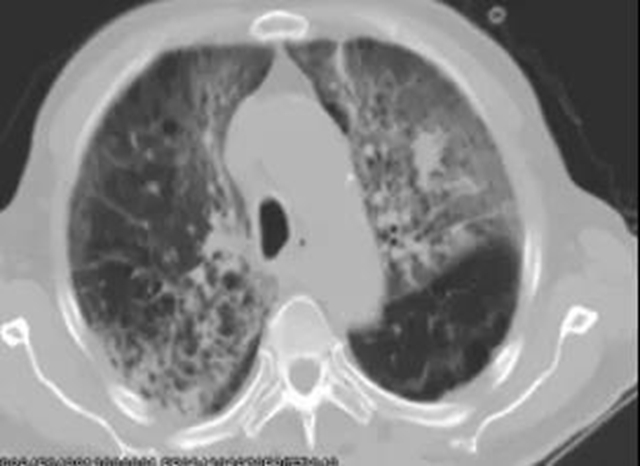

2、急性放射性肺损伤

患者因个体差异、基础疾病(患有慢性肺病)、其他治疗(化疗药物)、吸烟等可能发生急性放射性肺损伤。

目前,临床可使用足量肾上腺皮质激素和抗菌素连续数周(2-3周,甚至1月)进行治疗。